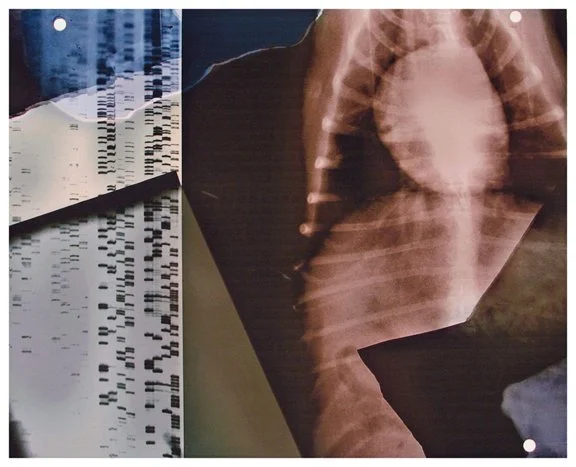

Insight is a series of collaged X-ray fragments, which were digitally composed into giclée prints. They speak not only of the body’s interior, but of the human experience it contains.

Drawn from DNA sequencing gels, mammograms, ultrasound scans, and cell cultures grown in Petri dishes, these compositions reframe diagnostic materials as metaphoric landscapes. What once served to identify illness becomes a language of line, texture, and light. They serve as a quiet meditation on fragility, resilience, and the unseen forces that shape us.

Each image in Insight is both an anatomical artifact and an artistic inquiry. Each one is part of my ongoing exploration of the relationship between Art, Science, and Medicine. Through digital layering and compositional play, I aim to dissolve the boundary between clinical detachment and emotional intimacy by inviting viewers to look inward and find meaning in the microscopic.